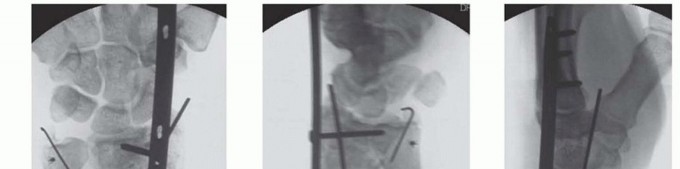

TECH FIG 3 • Final AP (A), oblique (B), and lateral (C) radiographic images. Displaced volar medial fracture fragments that are not reduced with this technique require a separate volar incision and appropriate buttress support.The biomechanical stability of spanning plates is strong and predictable. Behrens and Johnson, 2 studying the rigidity of external fixator configurations, demonstrated that rigidity is directly proportional to how close the longitudinal fixator bar is to the bone and the fracture. A bridge plate, resting directly against the radius proximally and metacarpals distally, therefore optimizes the conditions to obtain thestrongest possible fixator construct.A DRB plate fixed with a minimum of three screws at either end of the plate confers significantly more stability than would an external fixator used to stabilize a comparable fracture ( TECH FIG 3).181. Distal Radioulnar Joint ManagementDRUJ stability is assessed after radius reconstruction. If the DRUJ is stable, the limb is immobilized in a long-arm splint with the forearm in supination for the first 10 to 14 days postoperatively.If the DRUJ is unstable, and there are no contraindications to prolonging the operation, repair or reconstruction of DRUJ and triangular fibrocartilage complex is undertaken.If, however, the patient's condition does not allow the operation to be prolonged, the ulnar head is reduced manually into the sigmoid notch and the ulna is transfixed to the radius with a minimum of two 1.6-mm Kirschner wires passed proximal to the DRUJ.